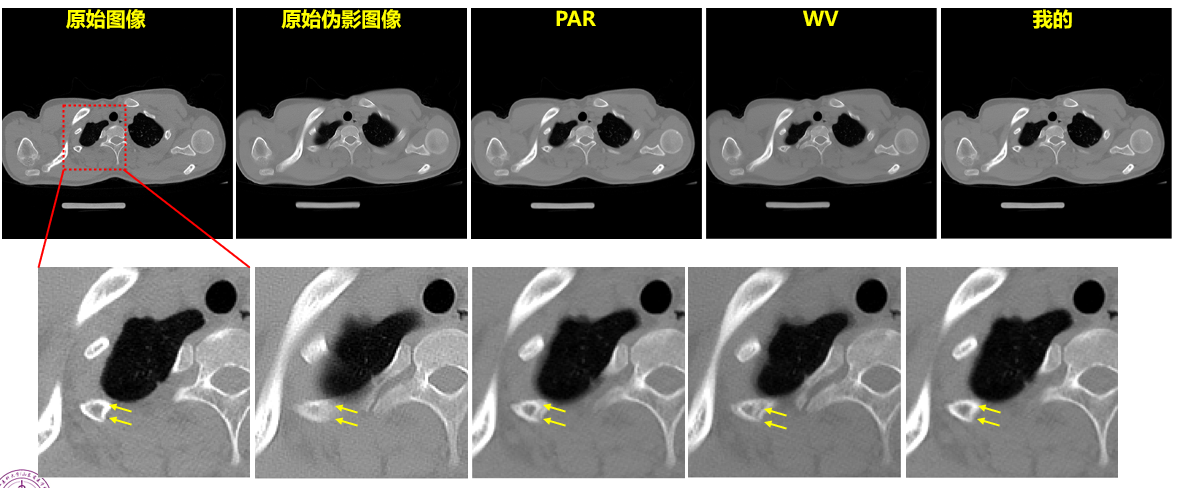

环状伪影的去除与传统方法的比较

临床上有很多不能自主呼吸或憋气的患者,比如意识不清的老人,儿童或有急诊外伤的患者,容易呈现模糊,影响诊断。如何去除不自主呼吸造成的运动伪影一直是热门临床难点之一。晁震博士提出了分布式径向基函数神经网络(RBFNN)结合特征先验来分析和处理每个伪像像素的方法,通过建立神经网络输入层,神经网络学习神经网络,分布式RBFNN训练等方法进行处理。

结果图像对比